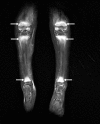

We report 3 cases of scurvy in children that occurred during a short period (2018) in a general pediatrics unit of a tertiary hospital for children in Paris. All children were around 3 years of age and were admitted for skeletal pain and altered general state, which mimicked infectious or malignant diseases. Their selective diet was not the prominent issue. The diagnosis of scurvy was delayed, after too many unnecessary examinations and medications. Bone imaging findings (X-ray and MRI) were a posteriori considered typical, but lesions were not easily identified as scurvy lesions because scurvy is not well-known by pediatricians and radiologists who should be mindful of this historical diagnosis VSports手机版. .